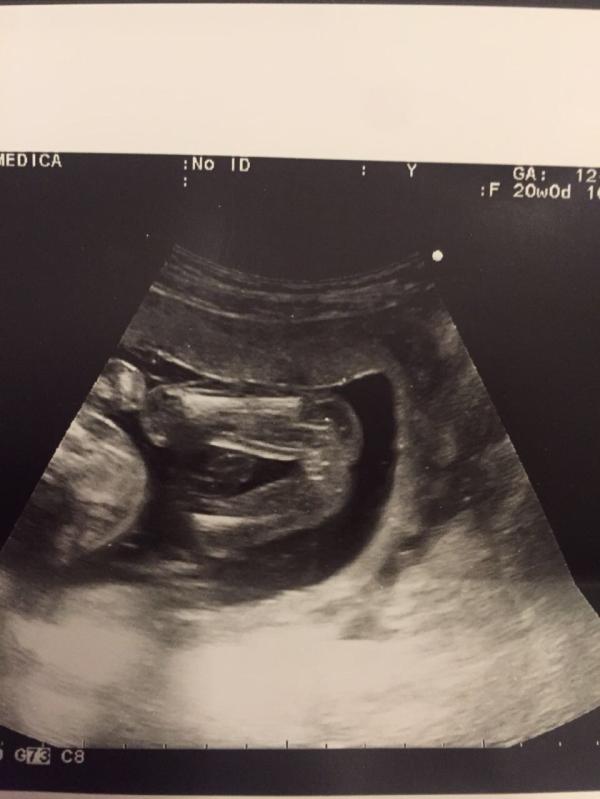

Ну вот и мне есть чем поделиться 😊 Сегодня у нас и ровно 20 недель, экватор, и второй скрининг УЗИ и очередной прием врача))) Ну начнем по порядку:

1. В пятницу в 19 недель и 4 дня, наконец-то почувствовала шевеления, точнее даже не шевеления, а хорошие такие толчки, когда ехала на работу) На следующий день, прямо с утра, мы уже хорошенько пнули пару раз, и с тех пор стараемся утром и вечером отпинать маму, причем в самый неожиданный момент)))

2. Наконец-то показались на УЗИ! До этого 2 раза...